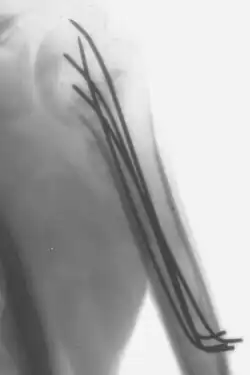

Kirschner wire

Kirschner wires or K-wires or pins are sterilized, sharpened, smooth stainless steel pins. Introduced in 1909 by Martin Kirschner, the wires are now widely used in orthopedics and other types of medical and veterinary surgery. They come in different sizes and are used to hold bone fragments together (pin fixation) or to provide an anchor for skeletal traction. The pins are often driven into the bone through the skin (percutaneous pin fixation) using a power or hand drill. They also form part of the Ilizarov apparatus.

- They can be used for definitive fixation if the fracture fragments are small (e.g. wrist fractures and hand injuries). In some settings they can be used for intramedullary fixation of bones such as the ulna.